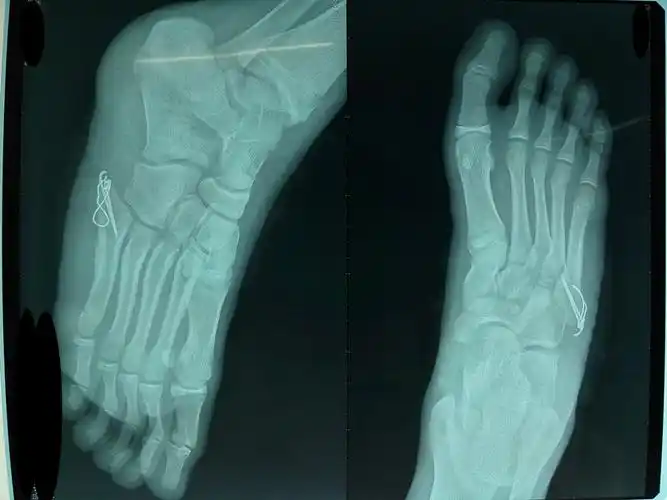

左脚第五跖骨基底骨折,附带片子,去医院看了说打上康达的高分子夹板

右足第五跖骨基底部骨折

第5跖骨基底部骨折

x线诊断为左足第5跖骨基底部骨折,请问严重吗?如何尽快恢复?